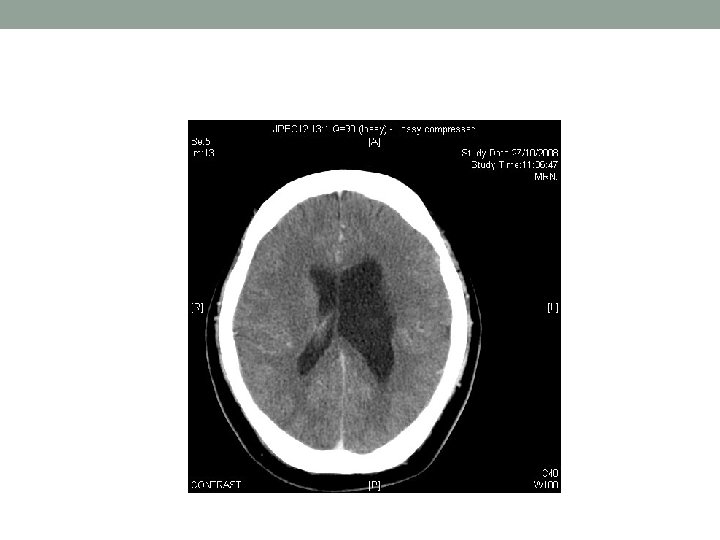

Day 2 • Review: • Neck soft • Plantar equivocal • Echo: • No effusion, LVEF OK, no obvious vegetation • CT brain: • no ICH • Focal dilatation of left lateral ventricle, ? porencephalic cyst due to previous insult in early infancy • LP: unremarkable